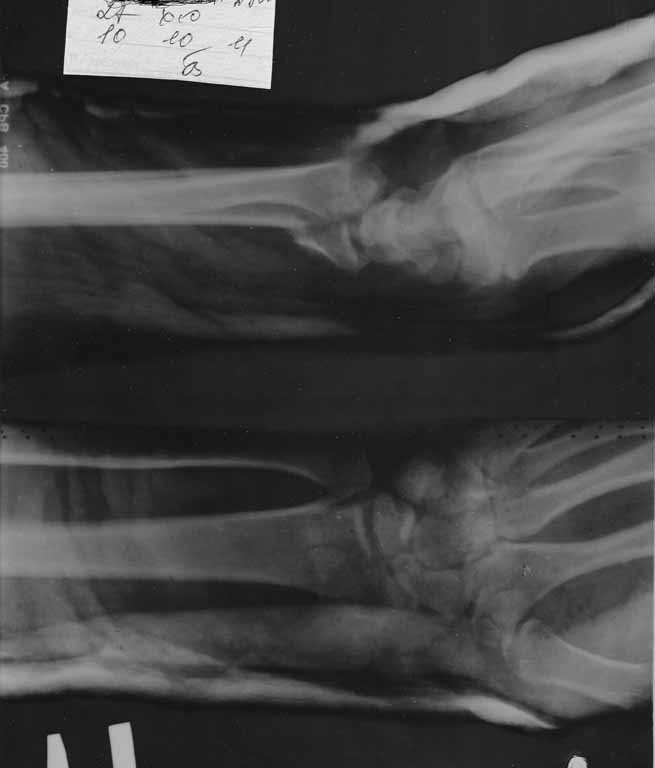

Re: перелом луча

послал Савранский Александр 11 Октябрь 2011, 10:42

в гипсе